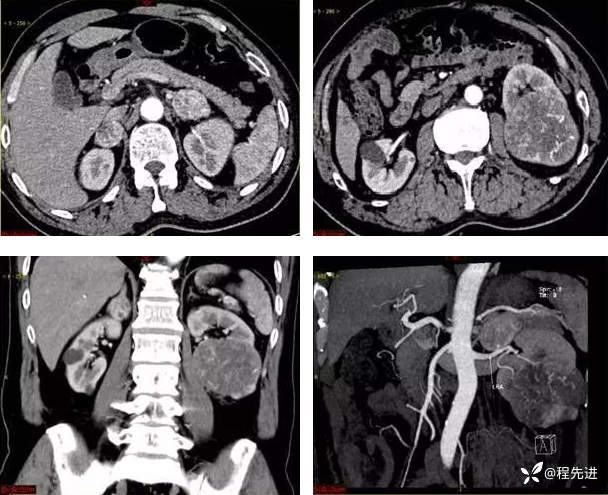

9月特别精彩病例|咳嗽伴咯血4月余,重点讨论胸部|结果已公布

患者性别:男

患者年龄:65岁

主诉:咳嗽伴咯血4月余

凝血功能:D-二聚体0.69 mg/L(<0.55mg/L)

生化:钙2.13mmol/L(2.20-2.65mmol/L),白蛋白37.60g/L(40.0-55.0g/L)

C反应蛋白9.05 mg/L(0.0-8.0mg/L)

肿瘤标志物:神经原特异性烯醇化酶22.1ng/mL(<16.3ng/mL)